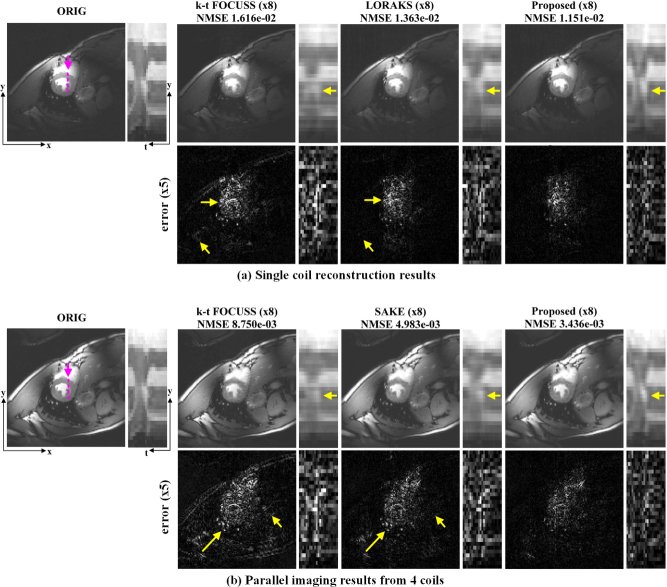

Using the sub-sampled k-space data at the acceleration factor of eight, the average NMSE values of k-t FOCUSS, LORAKS, and ALOHA, were , , and, , respectively. The sub-sampled data was collected according to a Gaussian distribution and included the four center lines around zero frequency. The average NMSE values were calculated using all temporal frames. These results confirmed that the proposed method outperformed k-t FOCUSS and LORAKS. As shown in Fig. 5(a), the temporal profile (indicated as a broken purple line) of the proposed reconstruction provided more accurate structures especially in the systole phase that were comparable to the true one, whereas the temporal variation in the k-t FOCUSS and LORAKS reconstruction became smoother and more blurry along the temporal dimension.

The NMSE values of the parallel dynamic imaging results from k-t FOCUSS, SAKE, and the proposed method using four coil k-space data were , and , respectively, which quantitatively showed that the proposed method outperformed k-t FOCUSS and SAKE. Reduced residual artifacts were perceivable in the ALOHA difference images in Fig. 5(b). Moreover, the temporal profiles of the proposed reconstruction showed more accurate structures which were comparable to the true one, whereas the dynamic slice profile from k-t FOCUSS and SAKE showed smoother and more blurry transition. In particular, the proposed algorithm resulted in more accurate reconstructions of dynamic changes at the heart wall in the systole phase as shown in Fig. 5(b).